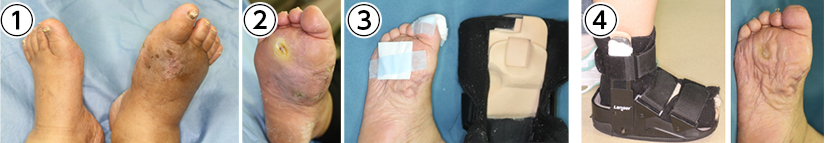

傷の免荷

傷は押されたり、擦れたりすると治りません。様々な部位の傷に対応した免荷装具の装着が、慢性創傷の治療では大切です。

①右第1趾潰瘍 ②使用した免荷サンダル ③治癒しました

①蜂窩織炎により右足が腫れています。

②踏み返し部に潰瘍が生じています。

③潰瘍の局所治療材料と免荷を目的とした中敷きを装着。

④患部保護のため踏み返しを制限することで治癒しました。